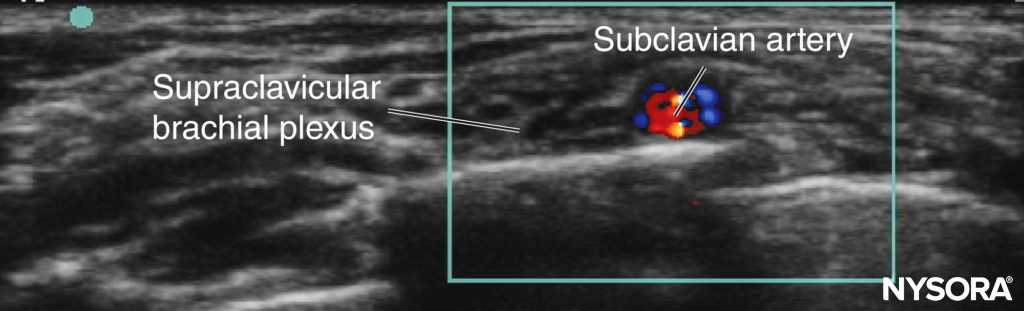

Supraclavicular Approach In the close anatomical relationships of children, only small probe movements are required to change from an interscalene view to a supraclavicular view. Prior to US, this block had been underused in children due to the close proximity of the cervical pleura. However, with appropriate training and mentorship, the sonoanatomy (Figure 3) becomes easy to understand, and the block generally becomes technically easy to perform. It is recommended that this block be performed only with the use of US.

FIGURE 3. Supraclavicular block in a child: probe position and relevant sonoanatomy.

Ultrasound-Guided Technique In the US-guided supraclavicular approach, the child is placed supine with a head ring and shoulder roll; this arrangement creates enough room for the anesthesiologist’s needling hand to approach from the posterior aspect. In the younger child, the first rib may not be fully ossified. Always use Doppler to identify potentially dangerous vessels in the proposed needle trajectory. The probe is positioned parallel to and touching the clavicle and is angled caudad, aiming into the thorax. An in-plane needling technique from the posterolateral to anteromedial direction is employed (see Figure 3).